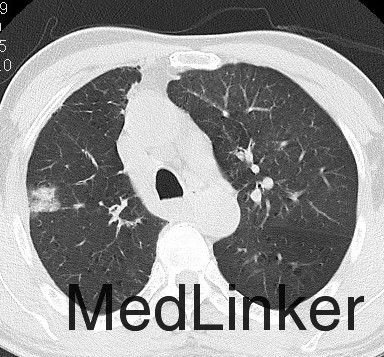

患者男,38岁。因刺激性咳嗽2月余入院。既往体健,无手术史,吸烟史20年,15支/d。CT检查示,左肺根部肿物,包绕左肺动脉干,并突人左肺动脉干内,考虑左肺中央型肺癌(图1)。

入院后检查未见远处转移,行左侧开胸探查。术中发现左肺门左肺动脉干处大块肿物,大小约为4.2 cm×3.8 cm,包绕左肺动脉干。游离左肺动脉干,可触及左肺动脉干内肿块,质地较硬,仍考虑中央型肺癌侵及肺动脉。术中决定行左全肺切除,依次切断左肺上下静脉及左主支气管,以血管闭合器闭合左肺动脉干,切除左全肺,清扫淋巴结。术后大体标本示,肺动脉干内球形肿物,表面光滑。病理检查示,左肺动脉干平滑肌肉瘤。免疫组化结果示,肿瘤起源于肺动脉平滑肌细胞。术后患者恢复良好,但拒绝行放化疗及其他治疗,于术后9个月死于远处转移。

肺动脉平滑肌肉瘤是一种非常罕见、预后极差的肿瘤[1]。多发生于青壮年,男女发病比例约为2:1。临床症状主要包括呼吸困难、咳嗽、胸痛和咯血。多数患者的死亡诊断为急性肺栓塞、肺动脉炎、肺动脉高压和肺癌等。肺动脉肉瘤在临床上易被误诊为中央型肺癌或肺动脉血栓[2-3]。本例患者术前CT诊断为左肺中央型肺癌。肺动脉肉瘤的主要CT影像表现:(1)占据肺动脉主干或近心端肺动脉分支管腔的低密度充盈缺损;(2)病变处肺动脉呈膨胀性改变;(3)肿瘤侵犯到肺动脉腔外。